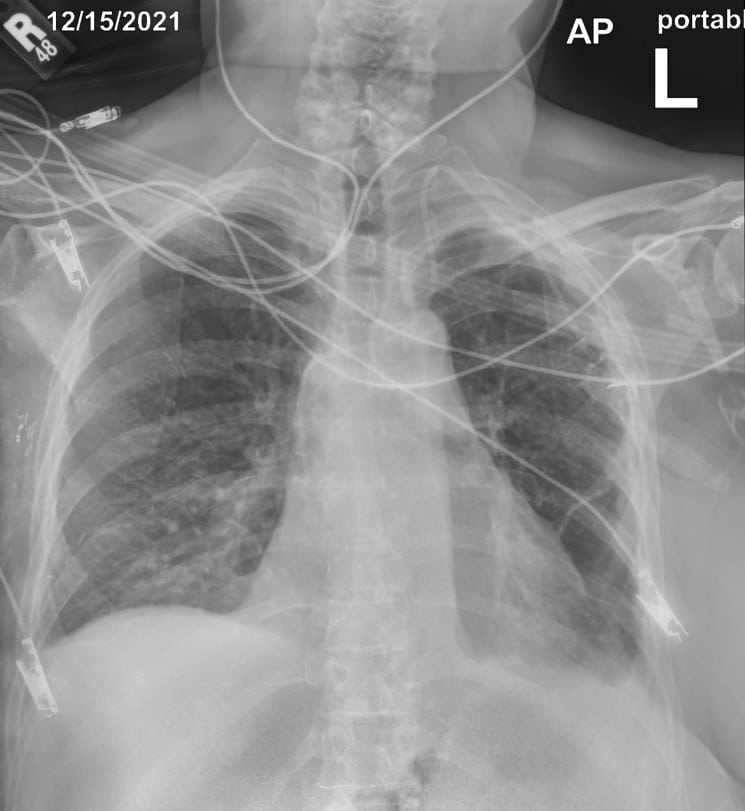

pneumothorax or other life-threatening chest injuries

device placement following emergency procedures

In this case, the conventional DR image shows subtle findings. The spectral soft-tissue image reduces overlying bone, making the pneumothorax more conspicuous. The corresponding bone-selective image highlights a rib fracture, a potential underlying cause of the pneumothorax.

Pneumothorax Evaluation

Soft-tissue images reduce rib overlap and may improve visualization of pneumothorax in trauma patients.